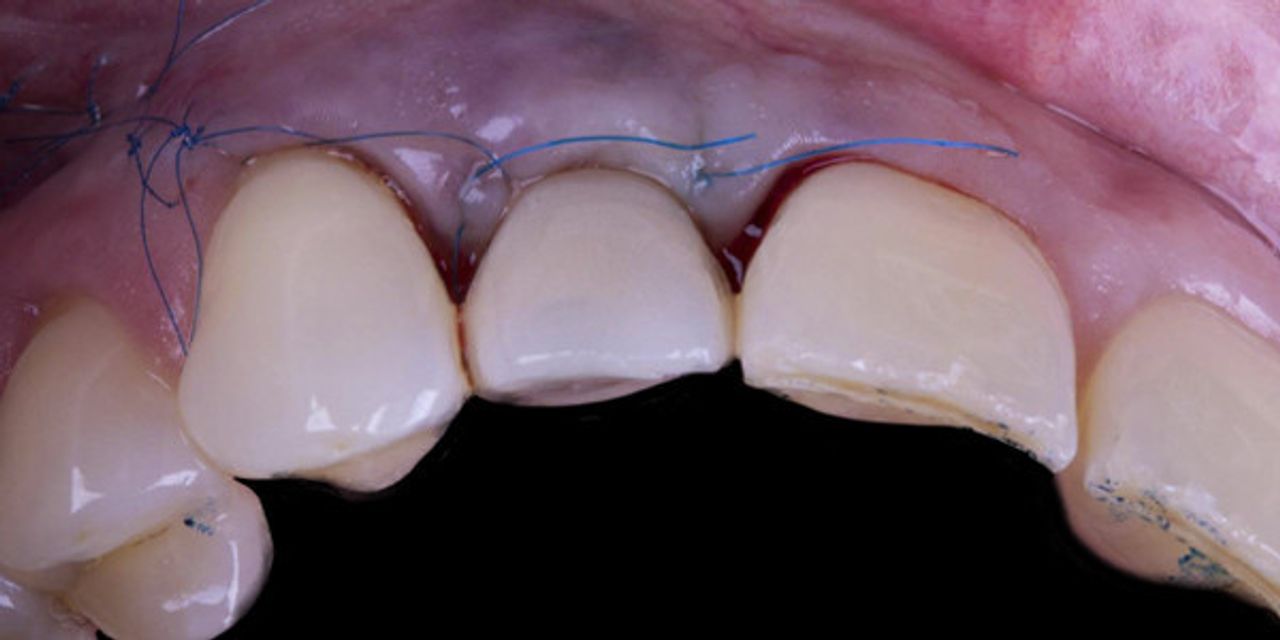

Потеря зубов приводит к резорбции костной ткани, это влияет на дальнейшую необходимость проведения аугментации (как костной, так и мягкотканной). Также это может стать причиной плохой эстетической стабильности в долгосрочной перспективе. Частичная экстракционная терапия (PET) - это методы, которые позволяют нам поддерживать костную ткань и, следовательно, предотвратить коллапс альвеолярной кости, создавая платформу для мягких тканей и кости, которая стабильна в течение длительного времени. Это большая проблема в эстетически значимых зонах.